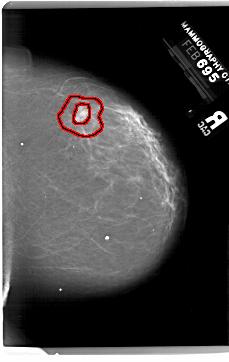

A_1999_1.LEFT_MLO

LEFT_MLO LINES 6346 PIXELS_PER_LINE 4246 BITS_PER_PIXEL 12 RESOLUTION 43.5 NON_OVERLAY

RIGHT_MLO LINES 6196 PIXELS_PER_LINE 4306 BITS_PER_PIXEL 12 RESOLUTION 43.5 OVERLAY

FILE: A_1999_1.RIGHT_MLO.OVERLAY

TOTAL_ABNORMALITIES 1

ABNORMALITY 1

LESION_TYPE MASS SHAPE IRREGULAR MARGINS SPICULATED

ASSESSMENT 5

SUBTLETY 3

PATHOLOGY MALIGNANT

TOTAL_OUTLINES 2

BOUNDARY

CORE